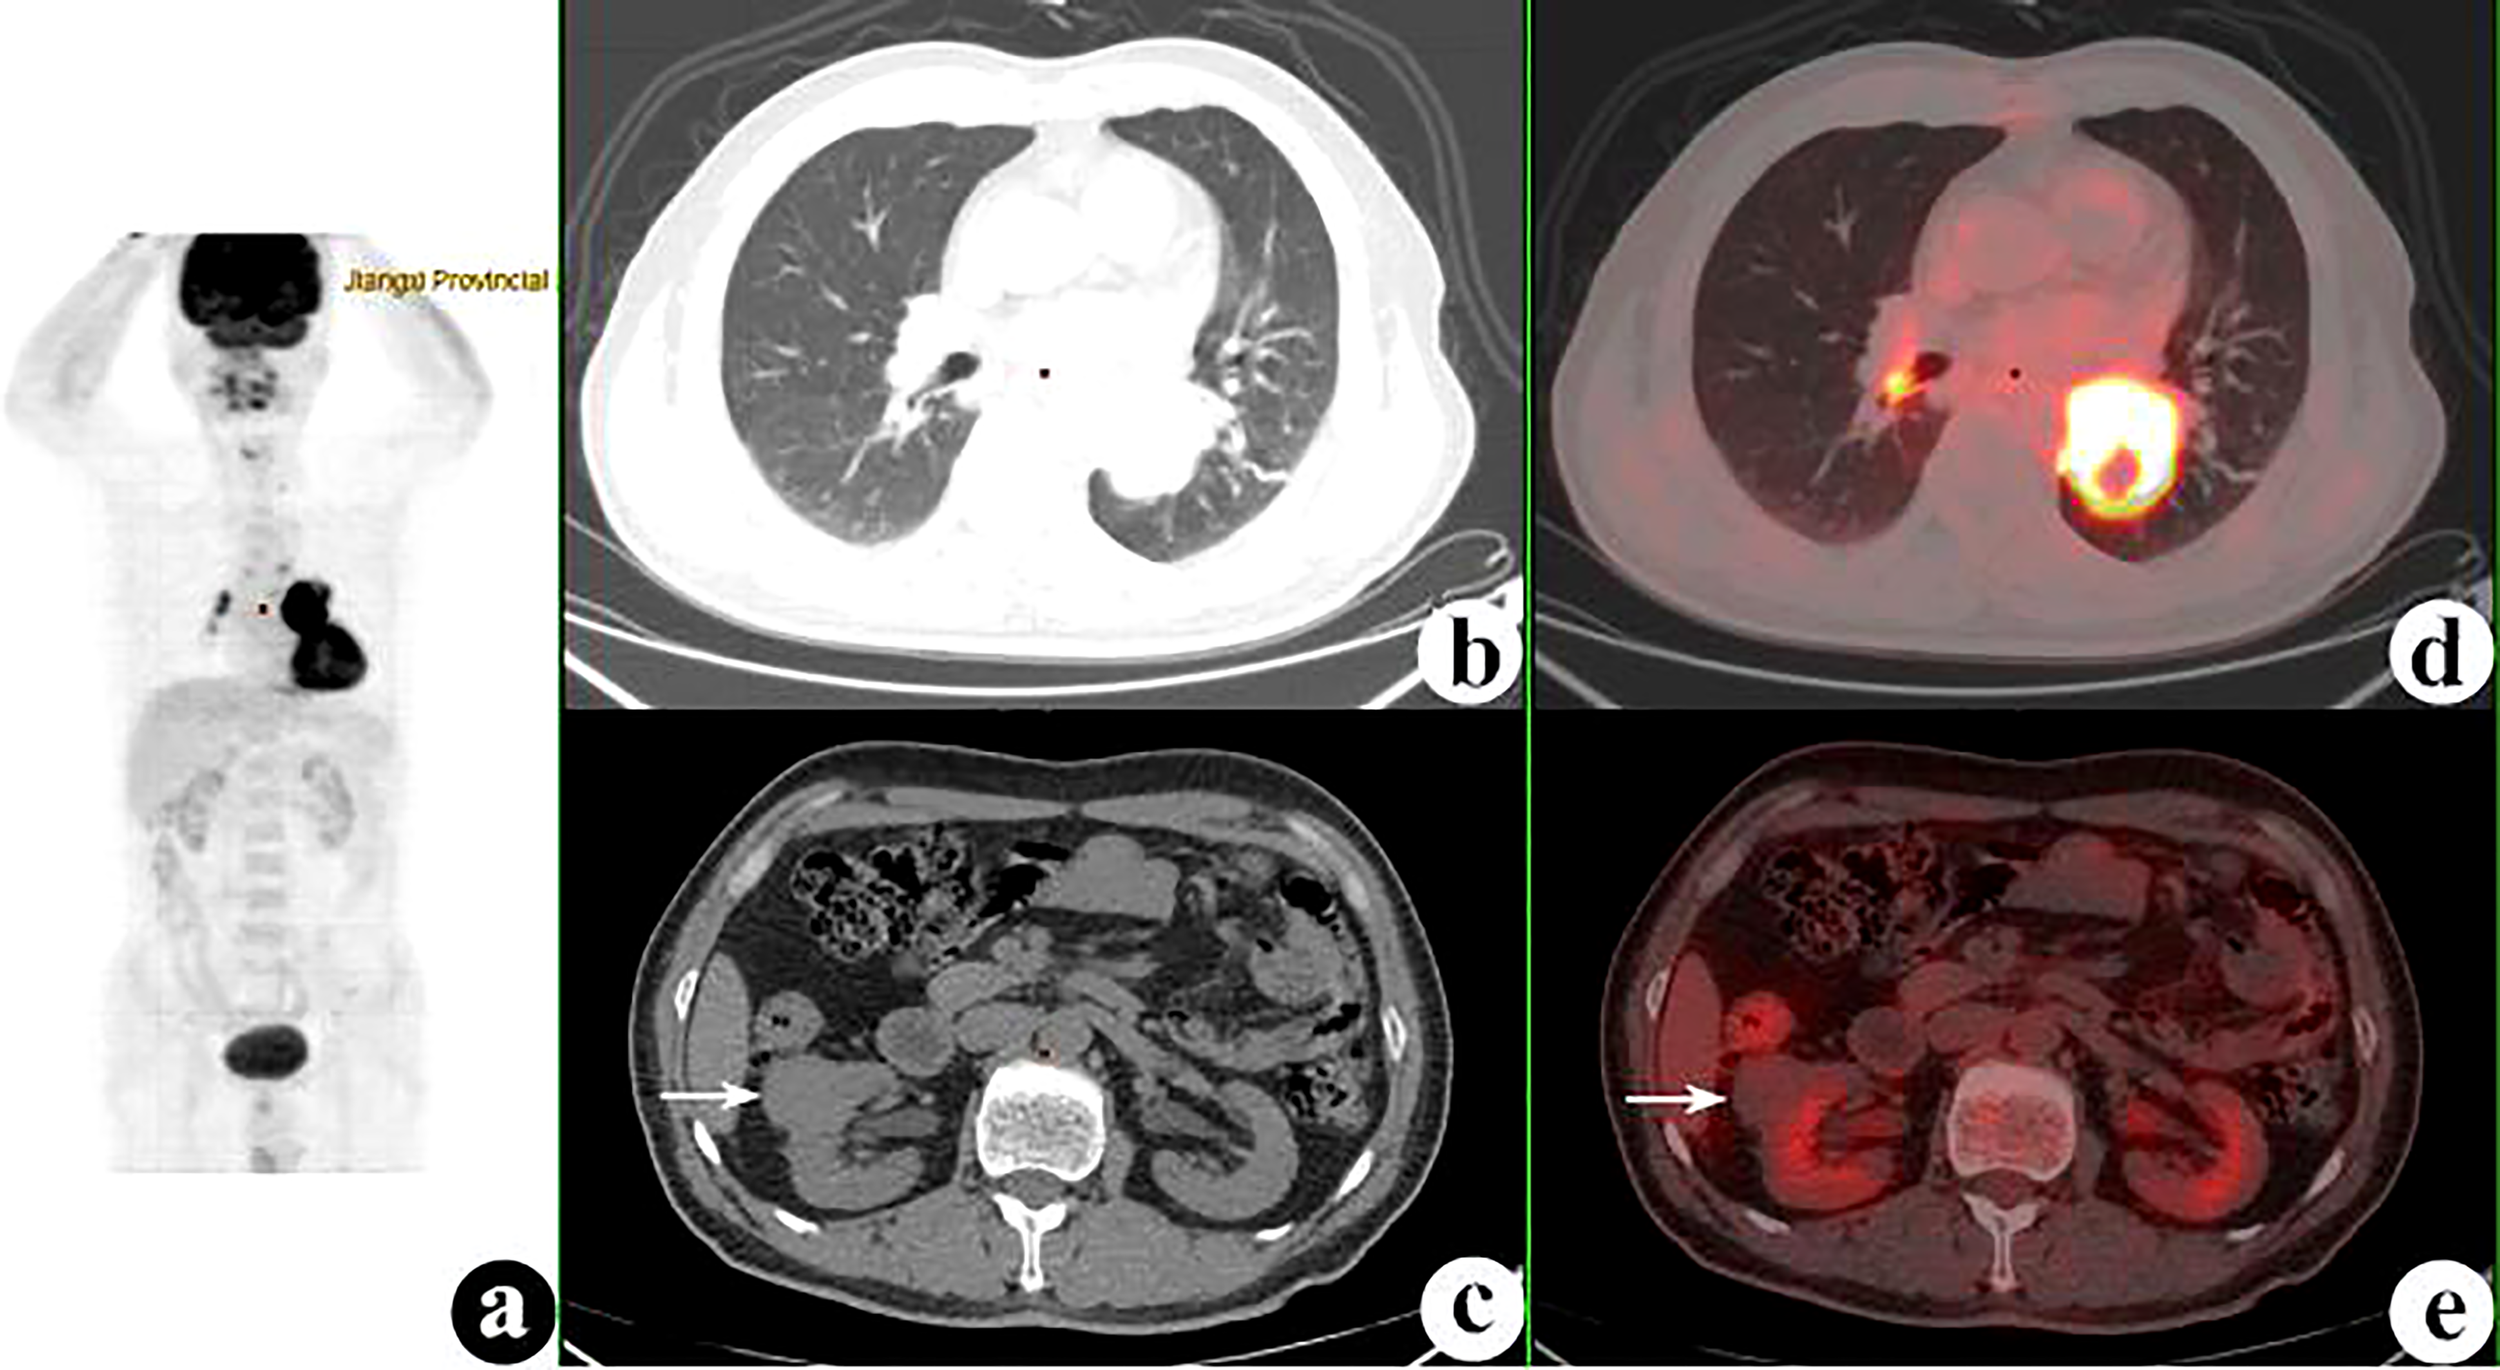

Figure 3 18F-fluorodeoxyglucose positron emission tomography/computed tomography (18F-FDG PET/CT) of a 62-year-old man with lung adenocarcinoma and hepatocellular carcinoma. PET/CT revealed a lobulated mass with central FDG uptake (maximum standardized uptake value, SUVmax = 8.9) and a 48 × 49-mm hypodense mass with SUVmax = 2.0 in the right hepatic lobe (white arrows). (A): PET maximum maximum intensity projection (MIP). (B, C): Axial CT. (D, E) Fusion images.

FIGURE 4

The 74 tumors had an average SUVmax of 12.3 ± 7.9 (range = 0.9–41.7). The primary tumors missed by PET/CT were retrieved and the SUVmax recalculated according to the confirmed site. The average SUVmax ratio, ΔSUVmax, and the DISUVmax of SMPMNs were 4.4 ± 6.9 (range = 0.3–26.7), 7.2 ± 7.6 (range = 0.0–34.0), and 50.3% ± 29.3% (range = 0.0%–96.3%), respectively. The ΔSUVmax values were ≥10.0 in 13 (35.1%) cases (Figure 2), 5.0 ≤ ΔSUVmax< 10.0 in 8 (21.6%) cases (Figure 3), and<5 in 16 (43.2%) cases (Figure 4).